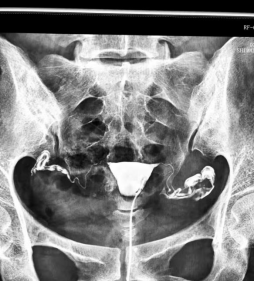

什么是子宫输卵管造影?

子宫输卵管造影(HSG)是指将造影注入子宫腔内,通过X-线观察记录造影剂的流动的过程,显示子宫、输卵管内腔的形态,以及造影剂流入腹腔后的弥散情况,从而对子宫输卵管形态功能做出诊断的不孕症检查措施。HSG是女性不孕症的初始检查之一,具有不可或缺的诊断价值。